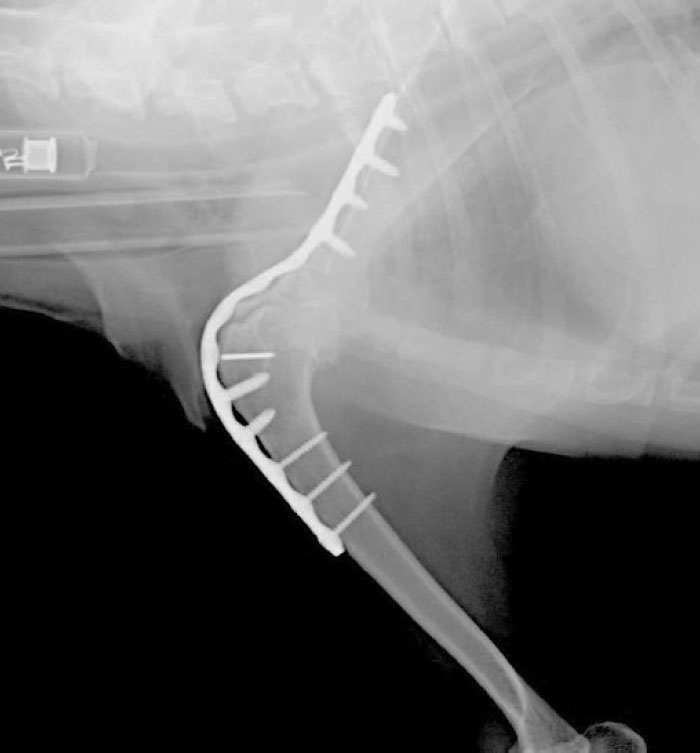

当院ではKYON社のALPS®︎(チタンプレートとチタンスクリュー)を使用した肩関節固定術を行っております。

犬の肩関節固定術では、関節軟骨の除去を確実に行うために、肩甲骨(関節窩)と上腕骨(骨頭)の両方の表面を外科的に削り、骨同士が直接接触する状態にします。

手術後